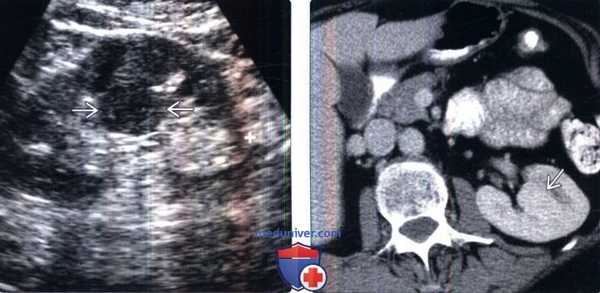

(Слева) УЗИ, сагиттальная косая плоскость через правую почку: у женщины 48 лет выявлен эхогенный клиновидный дефект на передней поверхности нижнего полюса.

(Справа) Несколько другое сечение правой почки у данной пациентки позволяет визуализировать расширение дефекта В в почечном синусе. Передняя сторона нижнего полюса — менее распространенная локализация дефекта паренхиматозного соединения. Обратите внимание на увеличенную печеночную эхогенность из-за стеатоза.